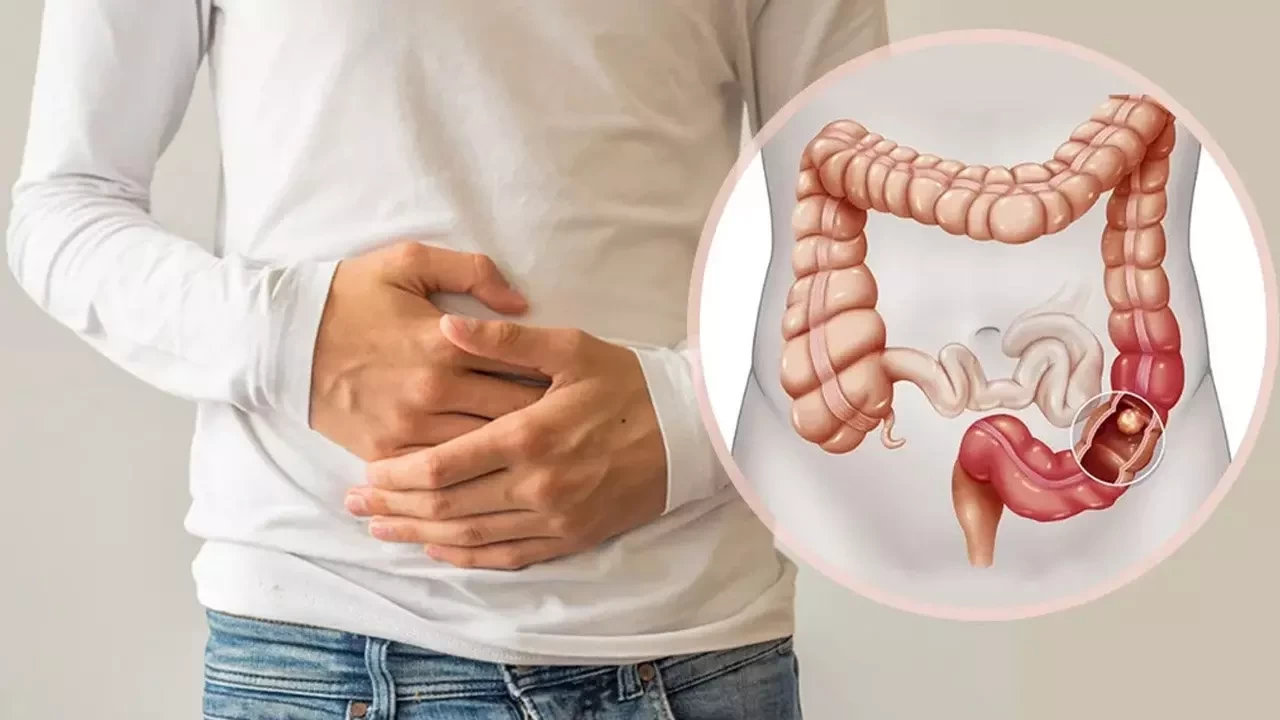

Kolon kanseri, kalın bağırsakta gelişen ve genellikle ileri yaş gruplarında teşhis edilen bir kanser türü olarak biliniyor. Ancak yeni veriler, genç yaşlarda da vakaların arttığını gösteriyor. Özellikle Batı tarzı beslenme, hareketsiz yaşam tarzı, obezite, aşırı şeker tüketimi ve çevresel faktörlerin bu artışa neden olduğu belirtiliyor.

Mart ayında yayınlanan Amerikan Kanser Derneği'nin (ACS) raporu, 40’lı yaşlarda ya da daha genç yaşlarda her beş yeni bağırsak kanseri vakasından birinin teşhis edildiğini gösterdi. Gençlerdeki vakaların genellikle daha ileri evrede tespit edildiği ve bu vakaların daha agresif tümör türlerine sahip olduğu ifade ediliyor.

ABD’de 2015-2021 yılları arasında yapılan ve yaklaşık 319 bin kolon kanseri vakasının incelendiği çalışmada, 18-44 yaş grubundaki vakaların yüzde 15 arttığı görüldü. Loyola Üniversitesi Tıp Merkezi’nden Dr. Kelley Chan, aynı dönemde 66 yaş ve üzeri hastalarda kolon kanseri teşhis oranlarının yüzde 20 azaldığını ancak gençlerdeki vakaların hızla arttığını belirtti.

Gençlerde kolon kanseri genellikle ileri evrede teşhis edildiğinden, tedavi süreci daha zorlu geçiyor. Dr. Chan, genç yaş grubundaki vakalarda erken teşhis yapabilmek için düzenli taramaların önemine vurgu yaparak, 45 yaş altındaki bireylerde kolon kanseri gelişimini anlamak için daha fazla araştırma yapılması gerektiğini belirtiyor.